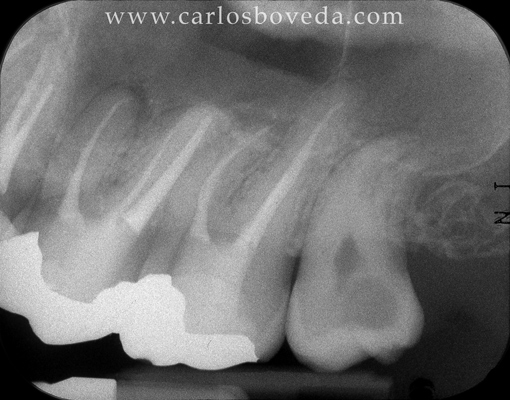

17